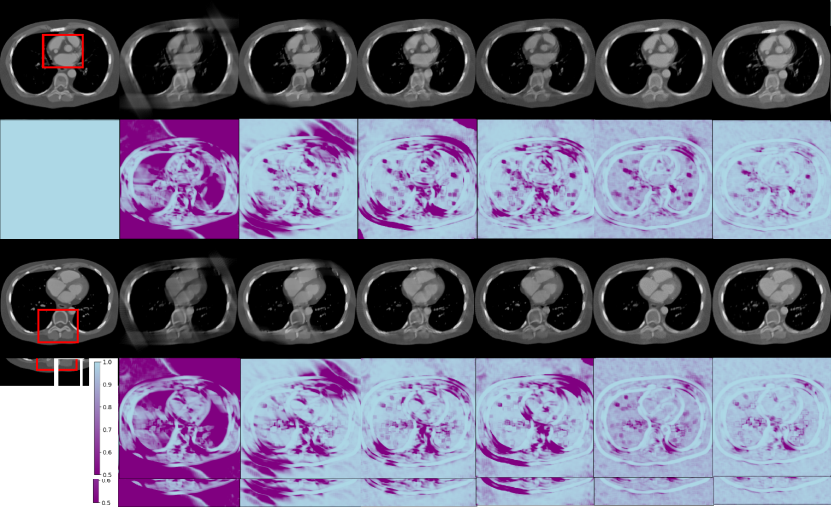

Refer to caption

Figure 2: Reconstruction results from the simulated dataset for different methods with a scanning angular range of 120° with Case 1 and Case 2. The 2ndsuperscript2𝑛𝑑2^{nd} and 4thsuperscript4𝑡4^{th} rows show the SSIM map compared to the ground truths. The display window is [540540-540 100010001000] HU.

Fig. 2 shows the representative reconstruction results for patient 153 across phases 100 and 112, utilizing different methods for 120-degree limited-angle reconstruction. The first and third rows display the reconstruction results, while the second and fourth rows provide the corresponding SSIM map for comparative analysis. For the 120-degree condition, most of the methods achieve satisfactory results, except for FBP and PDHG-TV, which are affected by strong limited-angle artifacts.

FBPConvNet and TomoGAN show compromised edge quality along oblique directions, while the Diffusion-MBIR and PSDM demonstrate superior edge preservation. However, the Diffusion-MBIR images lack the finer details that are perceivable in PSDM images.

For further comparison, two regions of interest (ROIs) are extracted from Cases 1 and Case 2, and subsequently magnified as in Fig. 3. Upon close examination of the structures, specifically those indicated by the red arrows, it is evident that the images are subject to blur and distortion when they are processed by PDHG-TV, FBPConvNet, and TomoGAN. Conversely, the Diffusion-MBIR and PSDM yield superior image quality. However, it should be noted that Diffusion-MBIR images are not entirely devoid of imperfections, as they continue to retain some noise and exhibit minor distortions at the locations indicated by the red arrows. Furthermore, when looking closely at the area indicated by the red circles, PSDM provides clearer reconstruction of the LAD branches compared to Diffusion-MBIR.